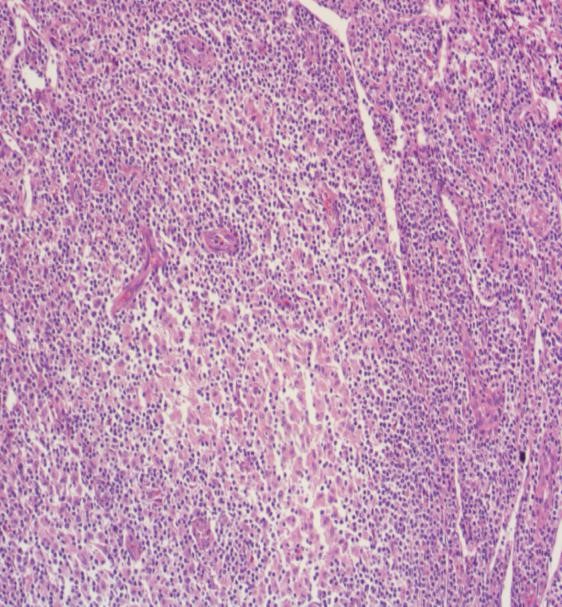

图文解析弥漫大B细胞淋巴瘤(DLBCL) – 91360智慧病理网

从一个会诊病例看《高级B细胞淋巴瘤》的过去、现在和将来-资讯频道-华夏病理网